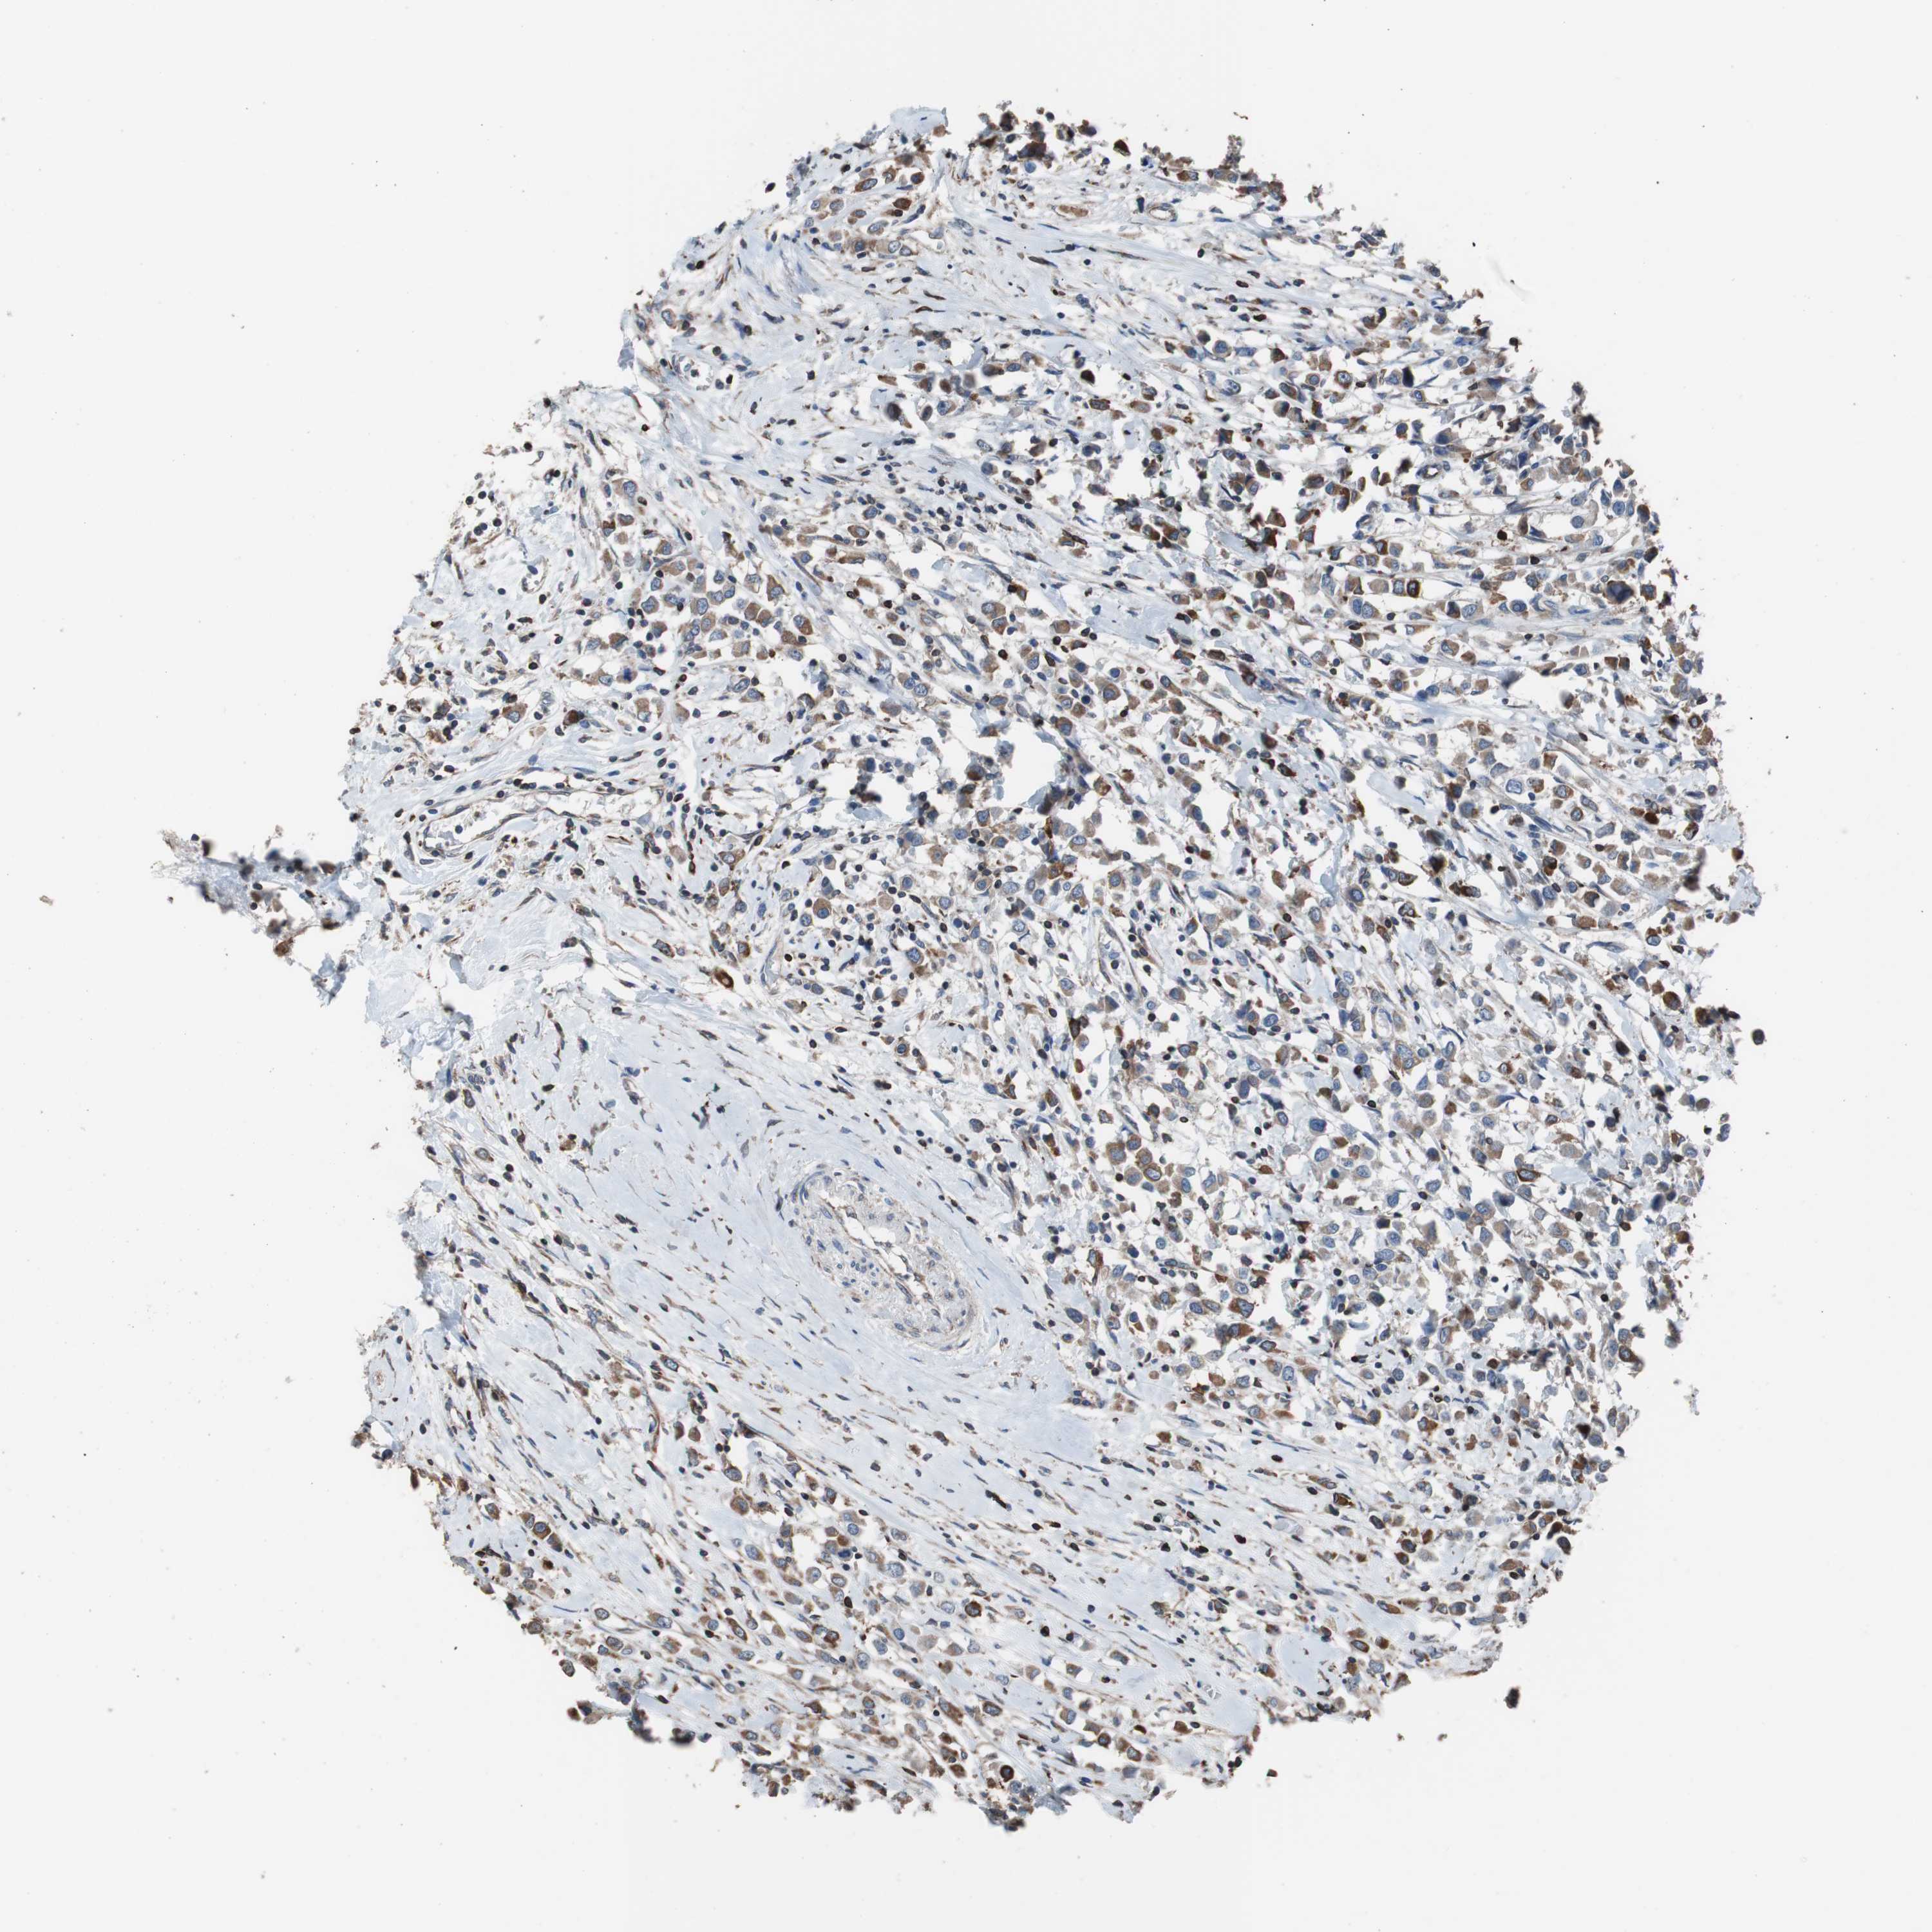

BRCA TCGA BRCA VALIDATION PROTEIN EXPRESSION

ANTIBODIES

AND

VALIDATION